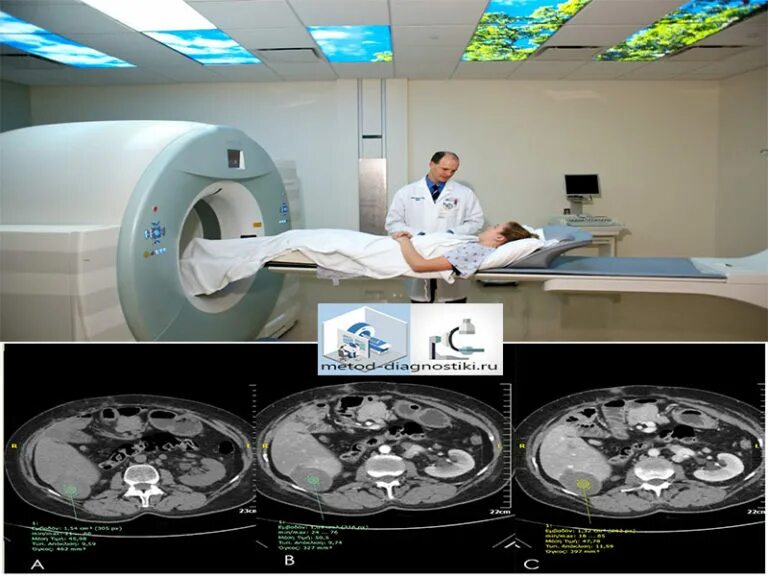

Мрт полностью